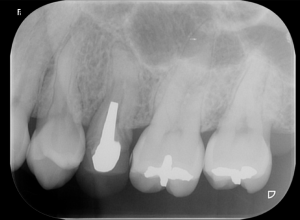

歯の神経を失うと歯はどうなるのか?

①歯根破折 歯の根っこが割れ、抜歯のリスクが高まります

歯の神経をとると歯がもろくなるため、歯が割れるリスクが高まります。割れた歯をそのまま残しておくことは困難で、基本的には抜歯になることが多いです。

②冠が入るため、エナメル質を全て失います

神経を取った歯は基本的には歯を覆うような被せ物が入ります。そのためエナメル質は全て喪失し、むし歯になりやすい歯となってしまいます

③神経の治療の成功率は低く、再発しやすい

神経の治療は医師のカンや経験による治療が多く、歯の中を盲目的に治療することが多いと言われています